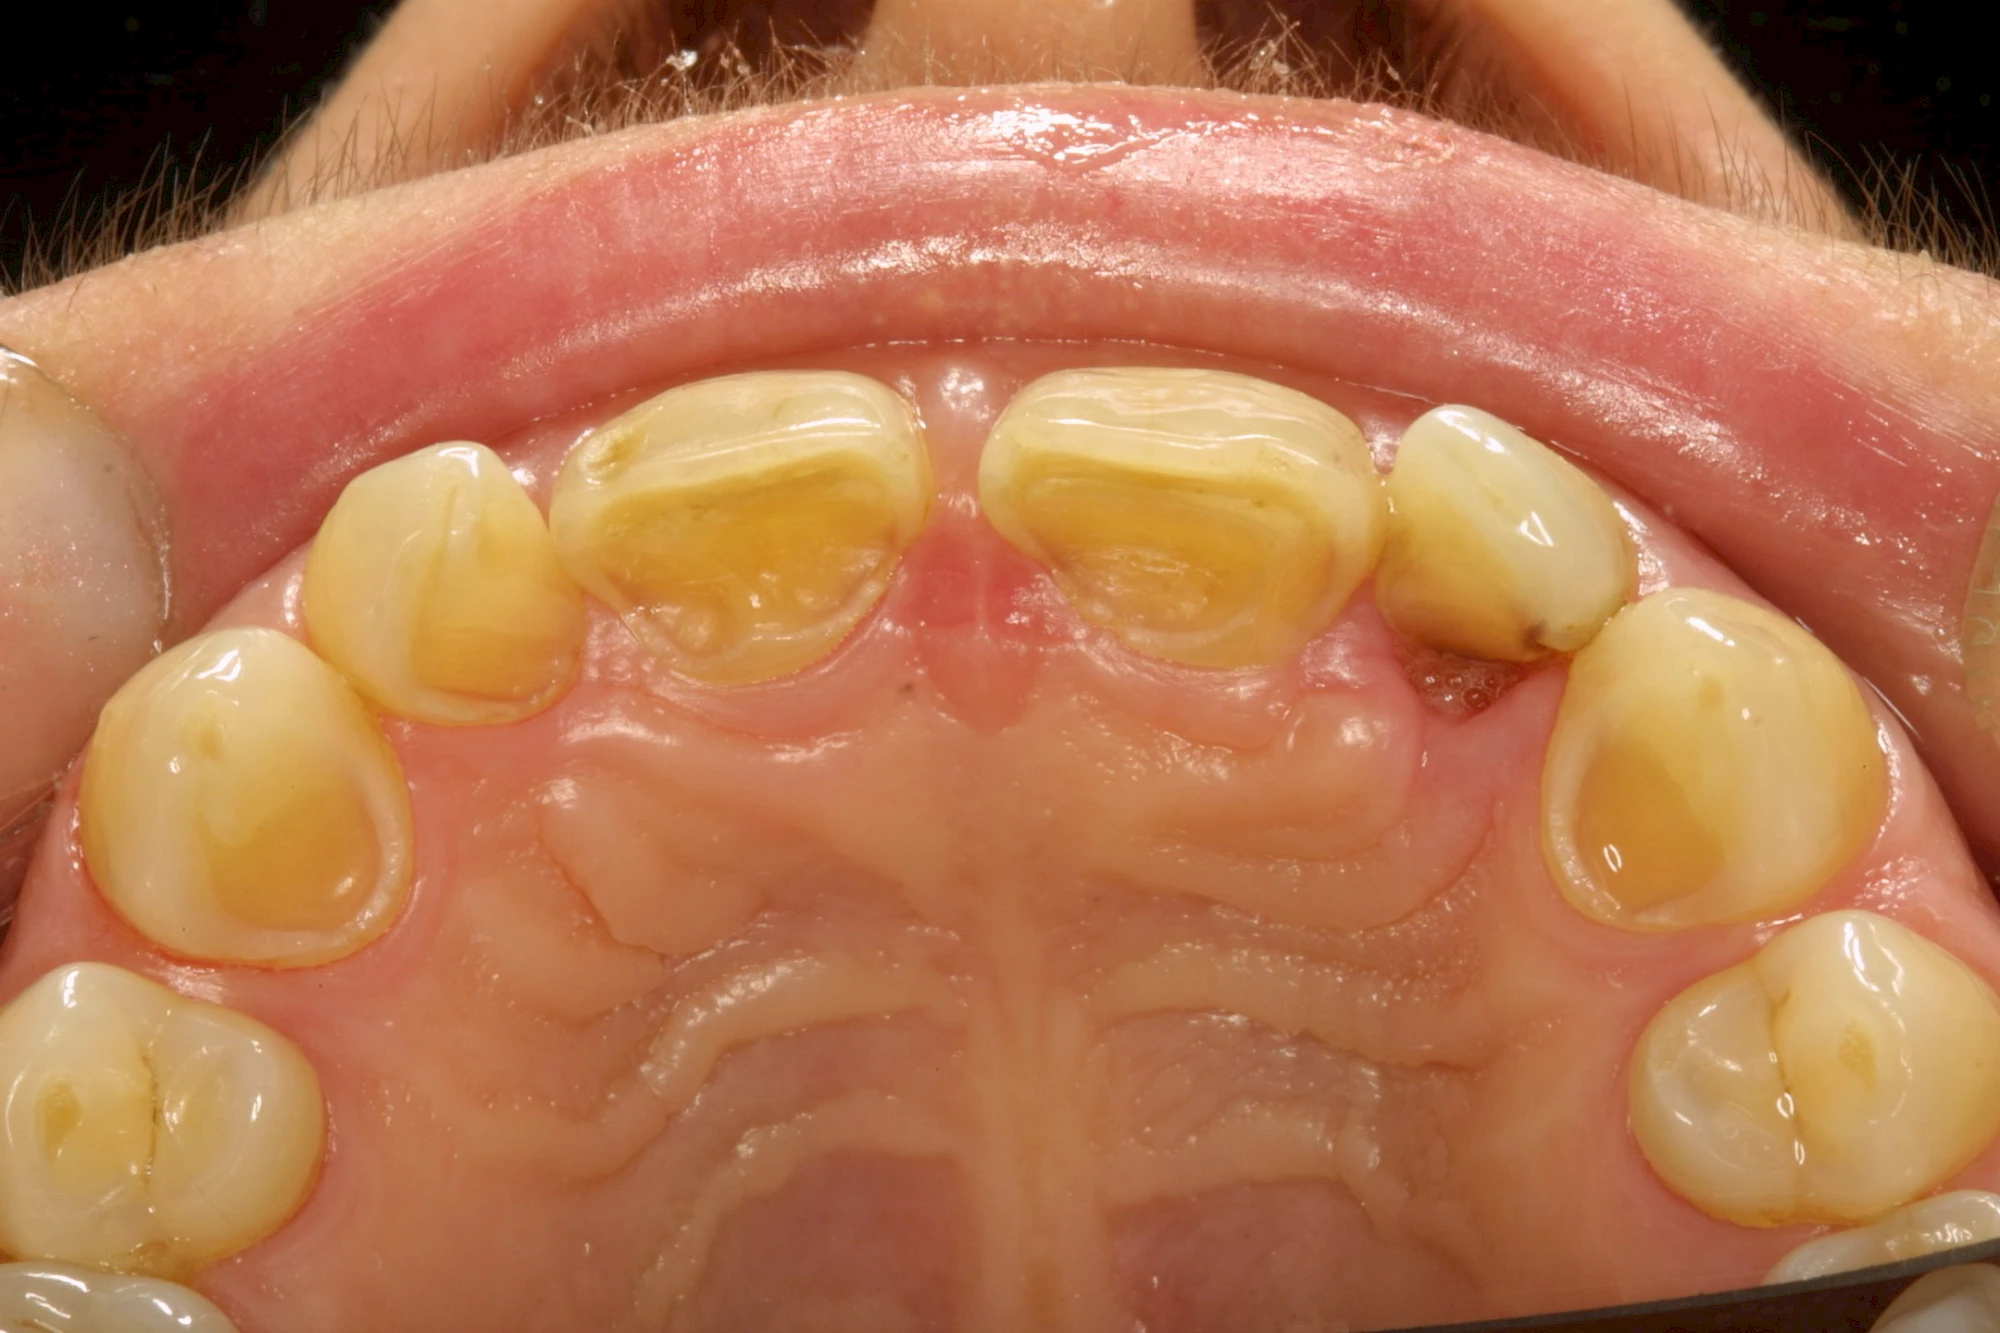

Auswaschung

Auswaschung (Erosion) dagegen ist eine Verschleißerscheinung der Zähne aufgrund von immer wiederkehrenden Säureangriffen durch die Nahrung, verstärkt zum Beispiel durch den Genuss säurehaltiger Getränke oder Speisen. Auch bei Menschen mit einer Essstörung (z. B. Bulimie) können die Zähne durch die Magensäure ausgewaschen erscheinen.